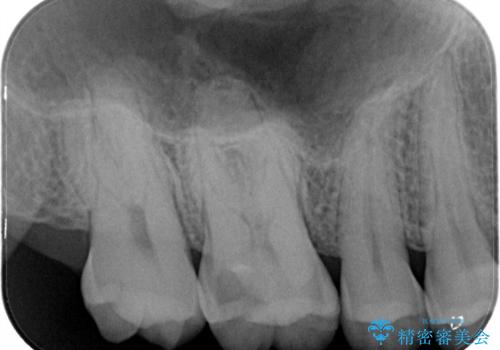

今回は虫歯が大きかったものの、ぎりぎり神経に達しておらず、セラミックインレー(つめもの)の治療のみで完了しました。初診時に虫歯を除去し、後日神経のテストをして正常反応を確認しました。

虫歯を徹底的に除去し、なおかつ神経に達しているかを慎重に判断するには、どうしても顕微鏡&長時間の診療が必要になりますが、保険外治療となります。